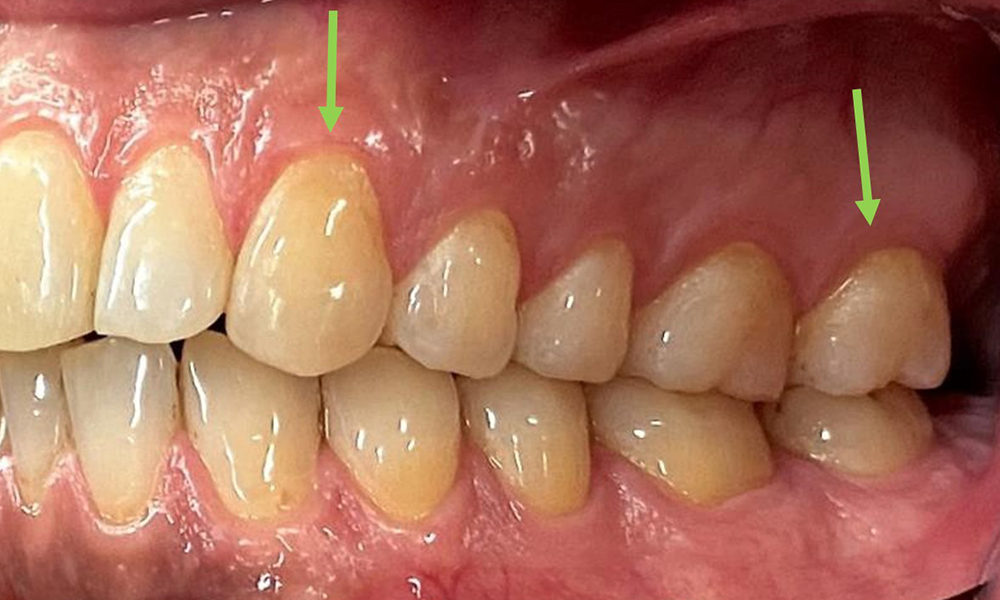

Close-up view of teeth

Fig. 5: Close-up view of teeth 45 to 47. The green arrows show dental attrition and erosions of the buccal cusps with partial enamel loss, © Dr R. Krapf

The patient has full dentition with a total of 28 teeth. There were noteworthy erosions and attritions. (Fig. 4, Fig. 5). Due to bruxism, the patient has been wearing a splint with an adjusted bite block at night for many years. The erosions were caused by long-term consumption of isotonic beverages. No periodontal bone loss or active caries were observed.